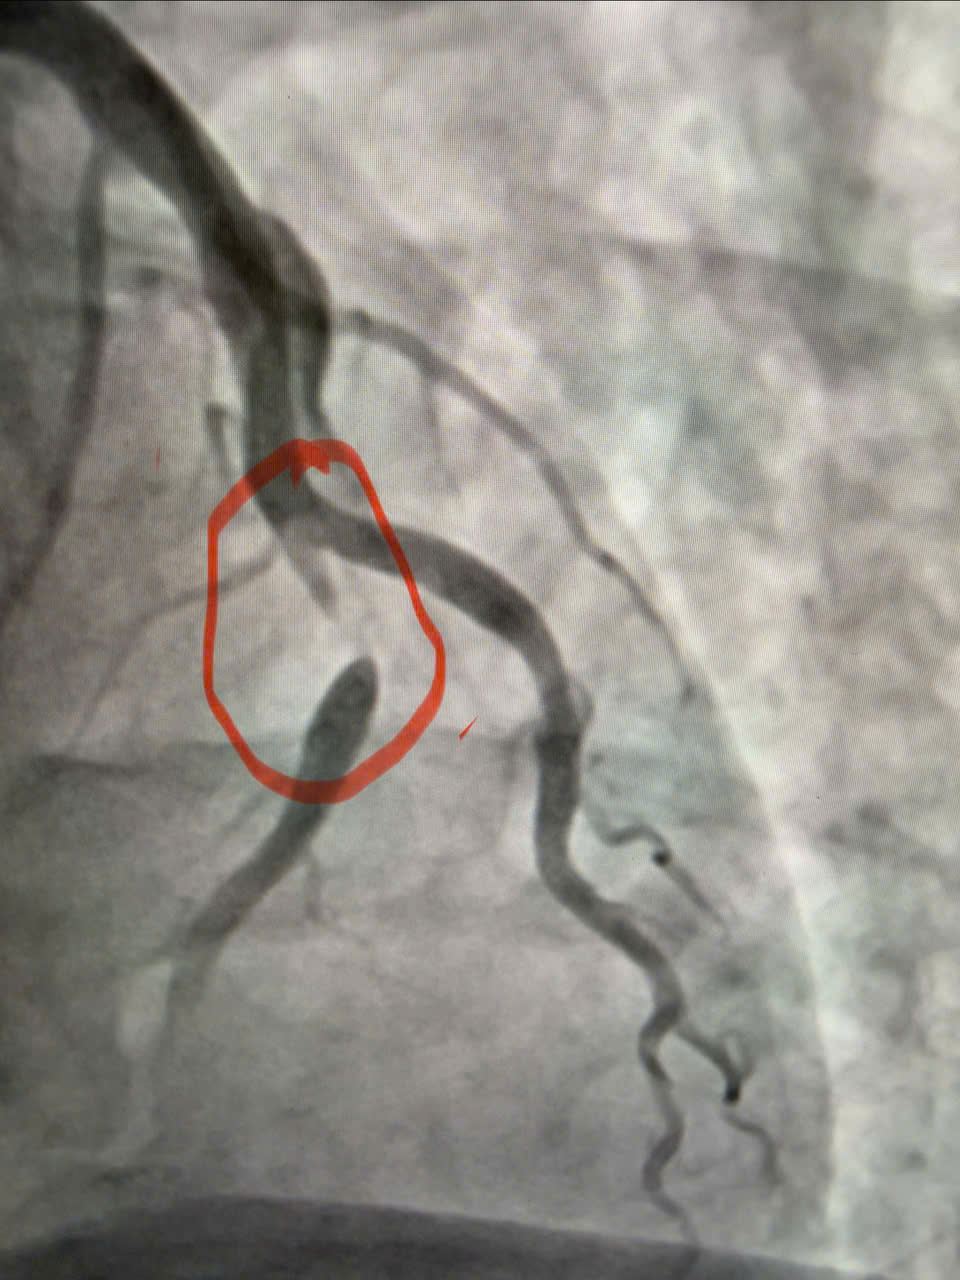

Hình ảnh chụp động mạch vành cho thấy hẹp 95% đoạn 1 động mạch liên thất trước – nhánh thủ phạm gây nhồi máu cơ tim cấp.

Ê-kíp bác sĩ Khoa Nội Tim mạch đã tiến hành chụp động mạch vành, kết quả cho thấy động mạch liên thất trước đoạn 1 – nhánh thủ phạm gây nhồi máu – bị hẹp tới 95%. Người bệnh được can thiệp nong và đặt stent động mạch vành, giúp tái thông dòng máu nuôi cơ tim, hạn chế tối đa tổn thương cơ tim và các biến chứng nguy hiểm.